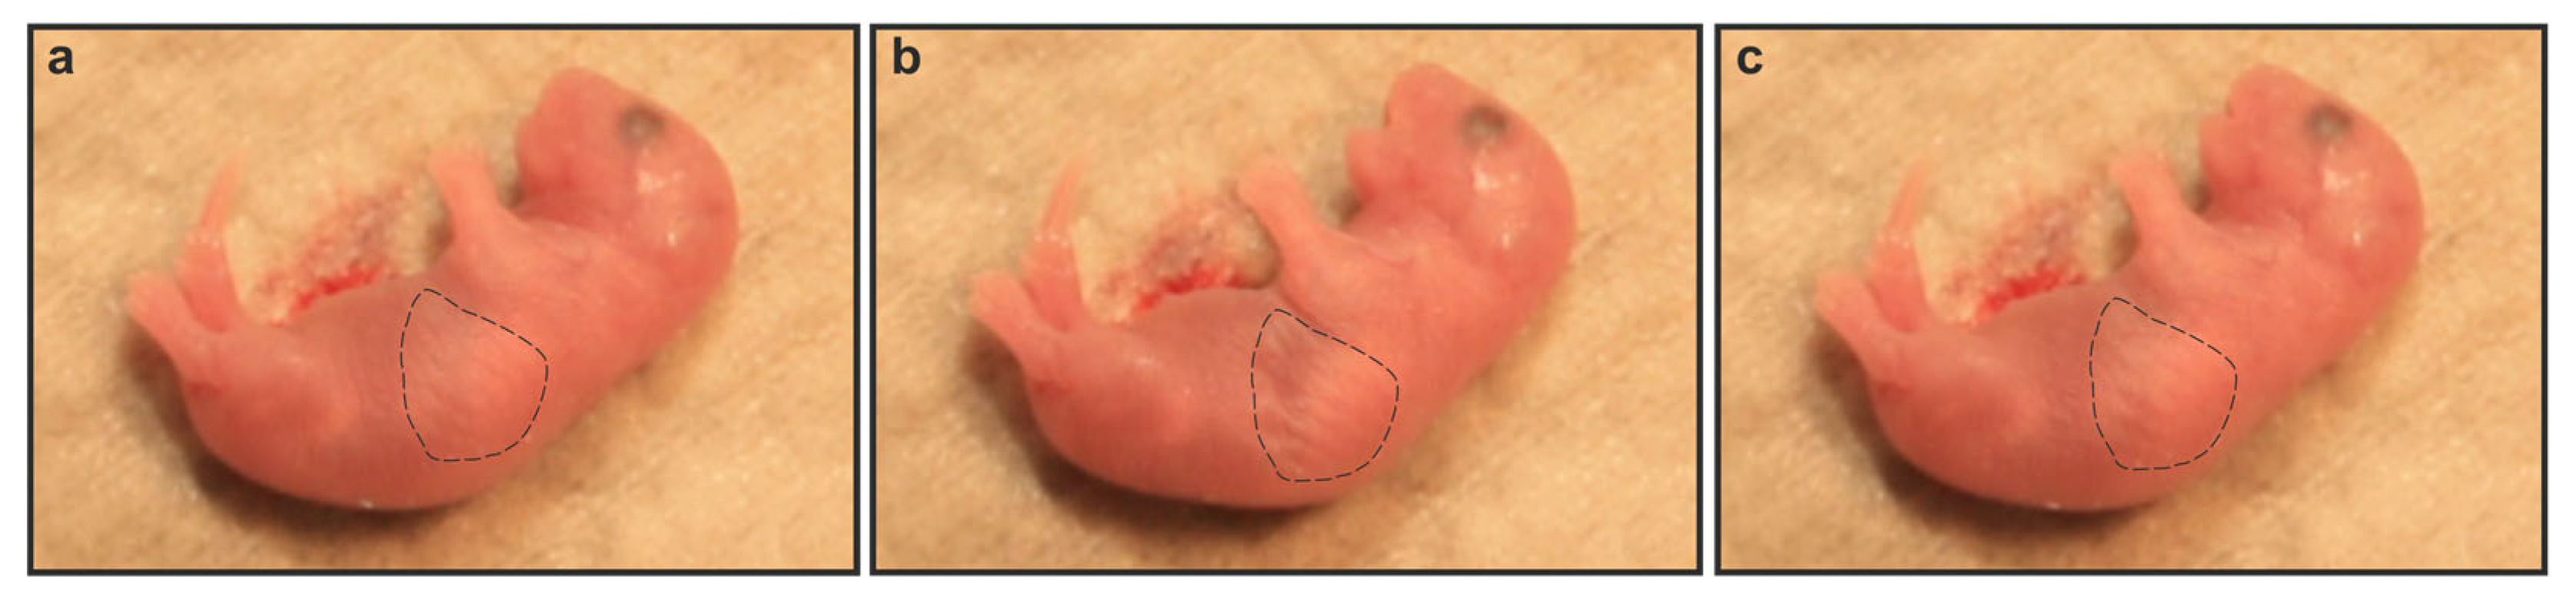

2.2. Gnai2-Deficiency Results in Lung Dysfunction in a Subset of Mice

2.3. Gnai2-Deficiency Reduces Alveolar Surface Area in Deceased Newborn Mice

2.4. Secreted Alveolar Surfactant Fails to Properly Unfold in Deceased Newborn Gnai2-Deficiency Mice